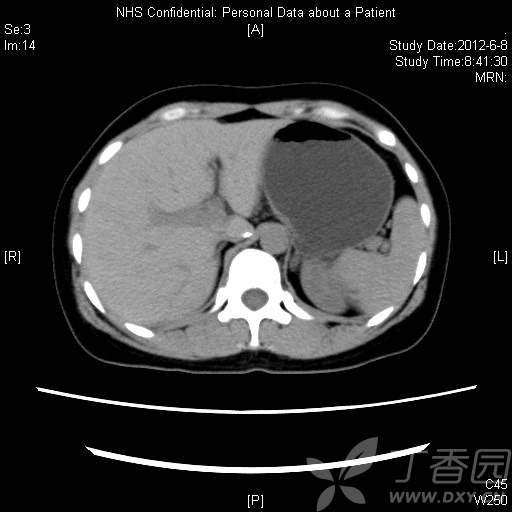

患者36岁女性,体检发现左肾实性占位,无自觉症状。

CT资料: